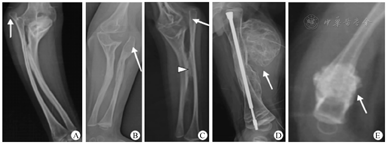

2000年,Glorieux等[6]首先提出了Ⅴ型OI的概念。该病呈常染色体显性遗传,在OI患儿中所占比例不到5%[7]。Ⅴ型OI与其他型患儿的临床表现不同,一般表现为不同程度的前臂骨间膜钙化、桡骨头脱位和增生性骨痂[8,9,10,11,12]。影像学表现见图1。

从目前的报道来看,前臂骨间膜钙化是几乎每个病例都存在的一个特征,多累及尺、桡骨骨间膜,也可累及胫腓骨骨间膜。尺、桡骨骨间膜钙化会导致前臂不同程度的旋前或旋后受限,并随着患儿年龄增长逐渐加重[6,8,9,10,11,12,13,14,15]。有研究报道骨间膜钙化在10岁前患儿中并不明显,最初仅表现为骨皮质增厚或内侧骨隆起[10,16]。但也有报道1岁就发生骨间膜钙化的患儿[17]。除了骨间膜,钙化还可以发生在肌肉起点、韧带甚至肌肉,比如腰方肌、内收肌、比目鱼肌在骨骼上附着点的钙化,胫腓韧带的钙化等[18]。

桡骨头脱位在许多患儿中都有发生,是肘关节畸形的原因之一[6,8,14,19]。桡骨头脱位首先表现为单侧,并随着患儿年龄增长而逐渐加重,后逐步发展至双侧。桡骨头脱位患儿大多有巨大尺骨鹰嘴和冠状突[16,17,20]。有学者认为,尺骨鹰嘴及冠状突异常增大可影响桡骨头发育,最终导致桡骨头脱位[21]。桡骨头脱位在Ⅰ、Ⅲ、Ⅳ型OI患儿中也偶有发生,发生率分别为1.5%、8.5%和6.5%;相比之下,桡骨头脱位在Ⅴ型OI患儿中似乎更为普遍,发生率可达约77%[20]。

高达65%的Ⅴ型OI患儿在骨折或外科手术后会出现增生性骨痂[11]。骨痂巨大呈圆形或椭圆形,增生性骨痂发生部位质地较硬、皮温较高,伴有疼痛、肿胀[20]。X线检查显示骨痂同股骨干界限分明,无骨皮质破坏,无骨膜反应,骨痂内密度低,巨大椭圆骨痂轮廓内可见不规则网格状分层形成;后期表现为巨大骨痂内密集钙化,密度同股骨干无明显差异,但股骨干界限仍可见,骨干皮质无破坏;术中可见骨痂内为大量脂肪组织,骨痂壁皮质菲薄,骨质脆弱[17]。

Ⅴ型OI患儿除了以上3个比较公认的特征外,还有很多其他特征,如:关节挛缩、椎体压缩、脊柱侧弯和长骨弯曲。其中,脊柱侧弯多见于女性,长骨弯曲多见于胫骨和腓骨[20]。影像学特征如前臂干骺端致密带和骨组织学上网状的层状结构也是Ⅴ型OI特征[8,9]。